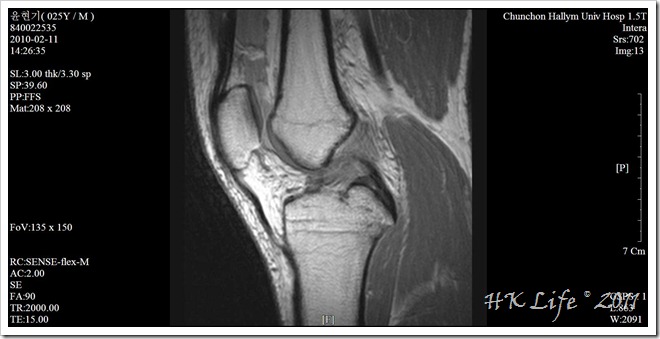

전방십자인대 수술 후 1년도 안되는 시점이었던지라 무릎상태도 좋지 않았고, 비행기 티켓팅이 이미 되어있는 상황이라 시간 및 장소 제한도 있는데다가, 그 때문에 그동안 머물던 밴쿠버가 아닌 토론토에서 여행을 시작해야만 하는 상황이었다.

01 knee mri

스키를 타다가 파열된 전방십자인대.